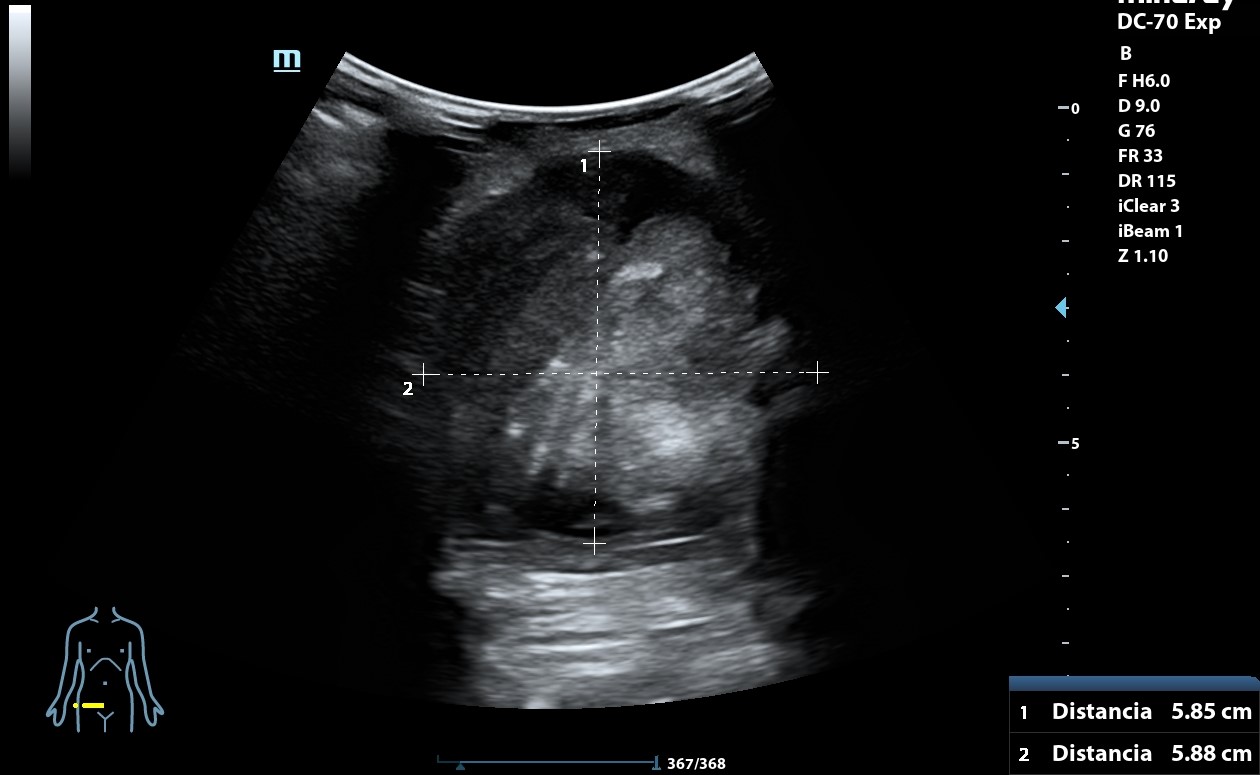

Ecografía clínica: arteria femoral dilatada con material hipoecoico heterogéneo en su pared lateral con un diámetro de 5,85 x 5,88 cm. Dilatación de aorta infrarrenal de 5,1 cm.

Diagnóstico: Aneurisma de arteria femoral derecha. aneurisma de aorta.